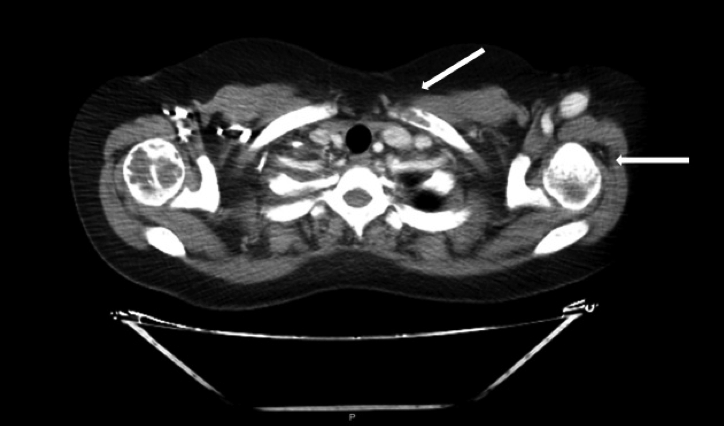

Ante la sospecha clínica de tumores pardos múltiples versus enfermedad metastásica se realiza IC con Oncología y en conjunto se solicitaron los siguientes estudios, que informaron como positivo: a) TAC de tórax, abdomen y pelvis (con contraste): leve enfisema centrolobulillar bilateral, opacidades nodulares con densidad de partes blandas (LSD y LSI). Resto de los órganos normales, no adenomegalias. Presencia de múltiples lesiones osteolíticas a nivel de todos los cuerpos vertebrales, esternón, región anterior de varias costillas, húmero, sacro, y porción visible de ambos ilíacos (Figuras 2, 3 . 4 A); b) TAC de cuello (con contraste): múltiples lesiones osteolíticas en la columna cervical.